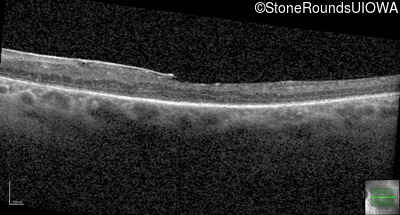

Optical Coherence Tomography - Right - 20/80 +1

Exemplar / OCT Stack

OCT Stack